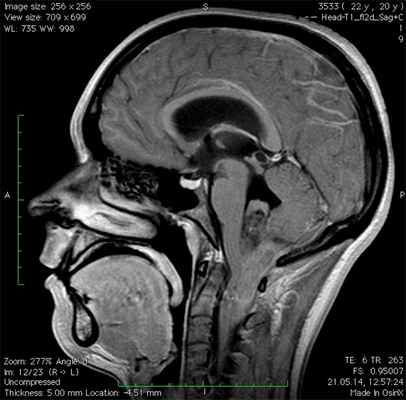

МРТ при миксопапиллярной эпендимоме позвоночника

а) Терминология:

• Медленно растущая глиома, развивающаяся из эпендимальных клеток конуса спинного мозга, терминальной нити и конского хвоста

б) Визуализация миксопапиллярной эпендимомы позвоночника:

• Протяженность опухоли обычно составляет 2-4 позвоночных сегмента:

о Может полностью заполнять собой пояснично-крестцовый дуральный мешок

• Овоидная, дольчатая или напоминающая сосиску форма

• КТ/рентгенография:

о ± расширение спинномозгового канала, истончение корней дуг, вдавление стенки позвонка

о Может распространяться в межпозвонковое отверстие, приводя к увеличению его объема

• Т1-ВИ: изоинтенсивность → гиперинтенсивность по отношению к спинному мозгу

• Т2-ВИ: практически всегда гиперинтенсивность по отношению к спинному мозгу:

о Гипоинтенсивная зона по краям опухоли = гемосидерин

• Т1-ВИ с КУ: интенсивное контрастное усиление

(Слева) На схеме сагиттального среза показана многоуровневая миксопапиллярная эпендимома конского хвоста. Опухоль хорошо васкуляризирована, с признаками старых внутриопухолевых кровоизлияний и свежего субарахноидального кровоизлияния вдоль дорзальной поверхности конуса спинного мозга. Медленный рост опухоли приводит к расширению спинномозгового канала и ремоделированию задней покровной пластинки тела позвонка.

(Справа) Фронтальный срез, Т1-ВИ: четко ограниченное интрадуральное экстрамедуллярное образование поясничного отдела позвоночника. Образование характеризуется преимущественно изоинтенсивным по отношению к спинному мозгу и корешкам сигналом. Практические 70% опухолей терминальной нити — это эпендимомы, в основном миксопапиллярного типа. (Слева) Сагиттальный срез, Т2-ВИ: распространенная интрадуральная опухоль, деформирующая конус спинного мозга и конский хвост. МЭ уникальны тем, что они обладают способностью накапливать внутриклеточно и в периваскулярных пространствах муцин, который дает гиперинтенсивность сигнала в Т1/Т2-режимах.

(Справа) Сагиттальный срез, Т1-ВИ с КУ: яркое и гомогенное усиление сигнала опухоли. Обратите внимание на наличие множества интрадуральных отсевов опухоли. Более мелкие опухоли обычно смещают корешки конского хвоста, тогда как более крупные сдавливают или полностью окружают их.